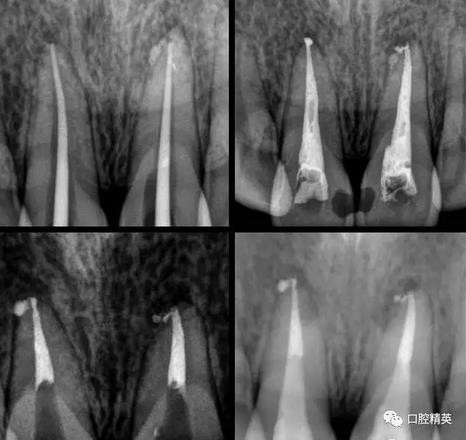

檢查:11,21近中鄰面可見樹脂類充填體,兩牙唇側(cè)根尖部有膿包狀突起,觸診疼痛,11,21無松動,叩診稍有不適,冷熱診檢查無反應(yīng),X-ray示11,21充填體底部近髓,根尖區(qū)無明顯異常影像。

處理:(初診)取原始模型,11,21開髓,拔髓,擴根,沖洗,CP碘仿棉捻開放。

(二診)取出開放物,雙氧水沖洗,氫氧化鈣糊劑加碘仿暫封2周。

(三診) 去除暫封物及糊劑,鹽水沖洗,隔濕,干燥,大錐度牙膠尖配合樹脂根充糊劑行根管充填,一周后復(fù)診。

(四診)11,21唇側(cè)膿腫基本消除,叩(-),預(yù)備樁道,置入纖維樁,備牙,取模,翻制臨時冠。